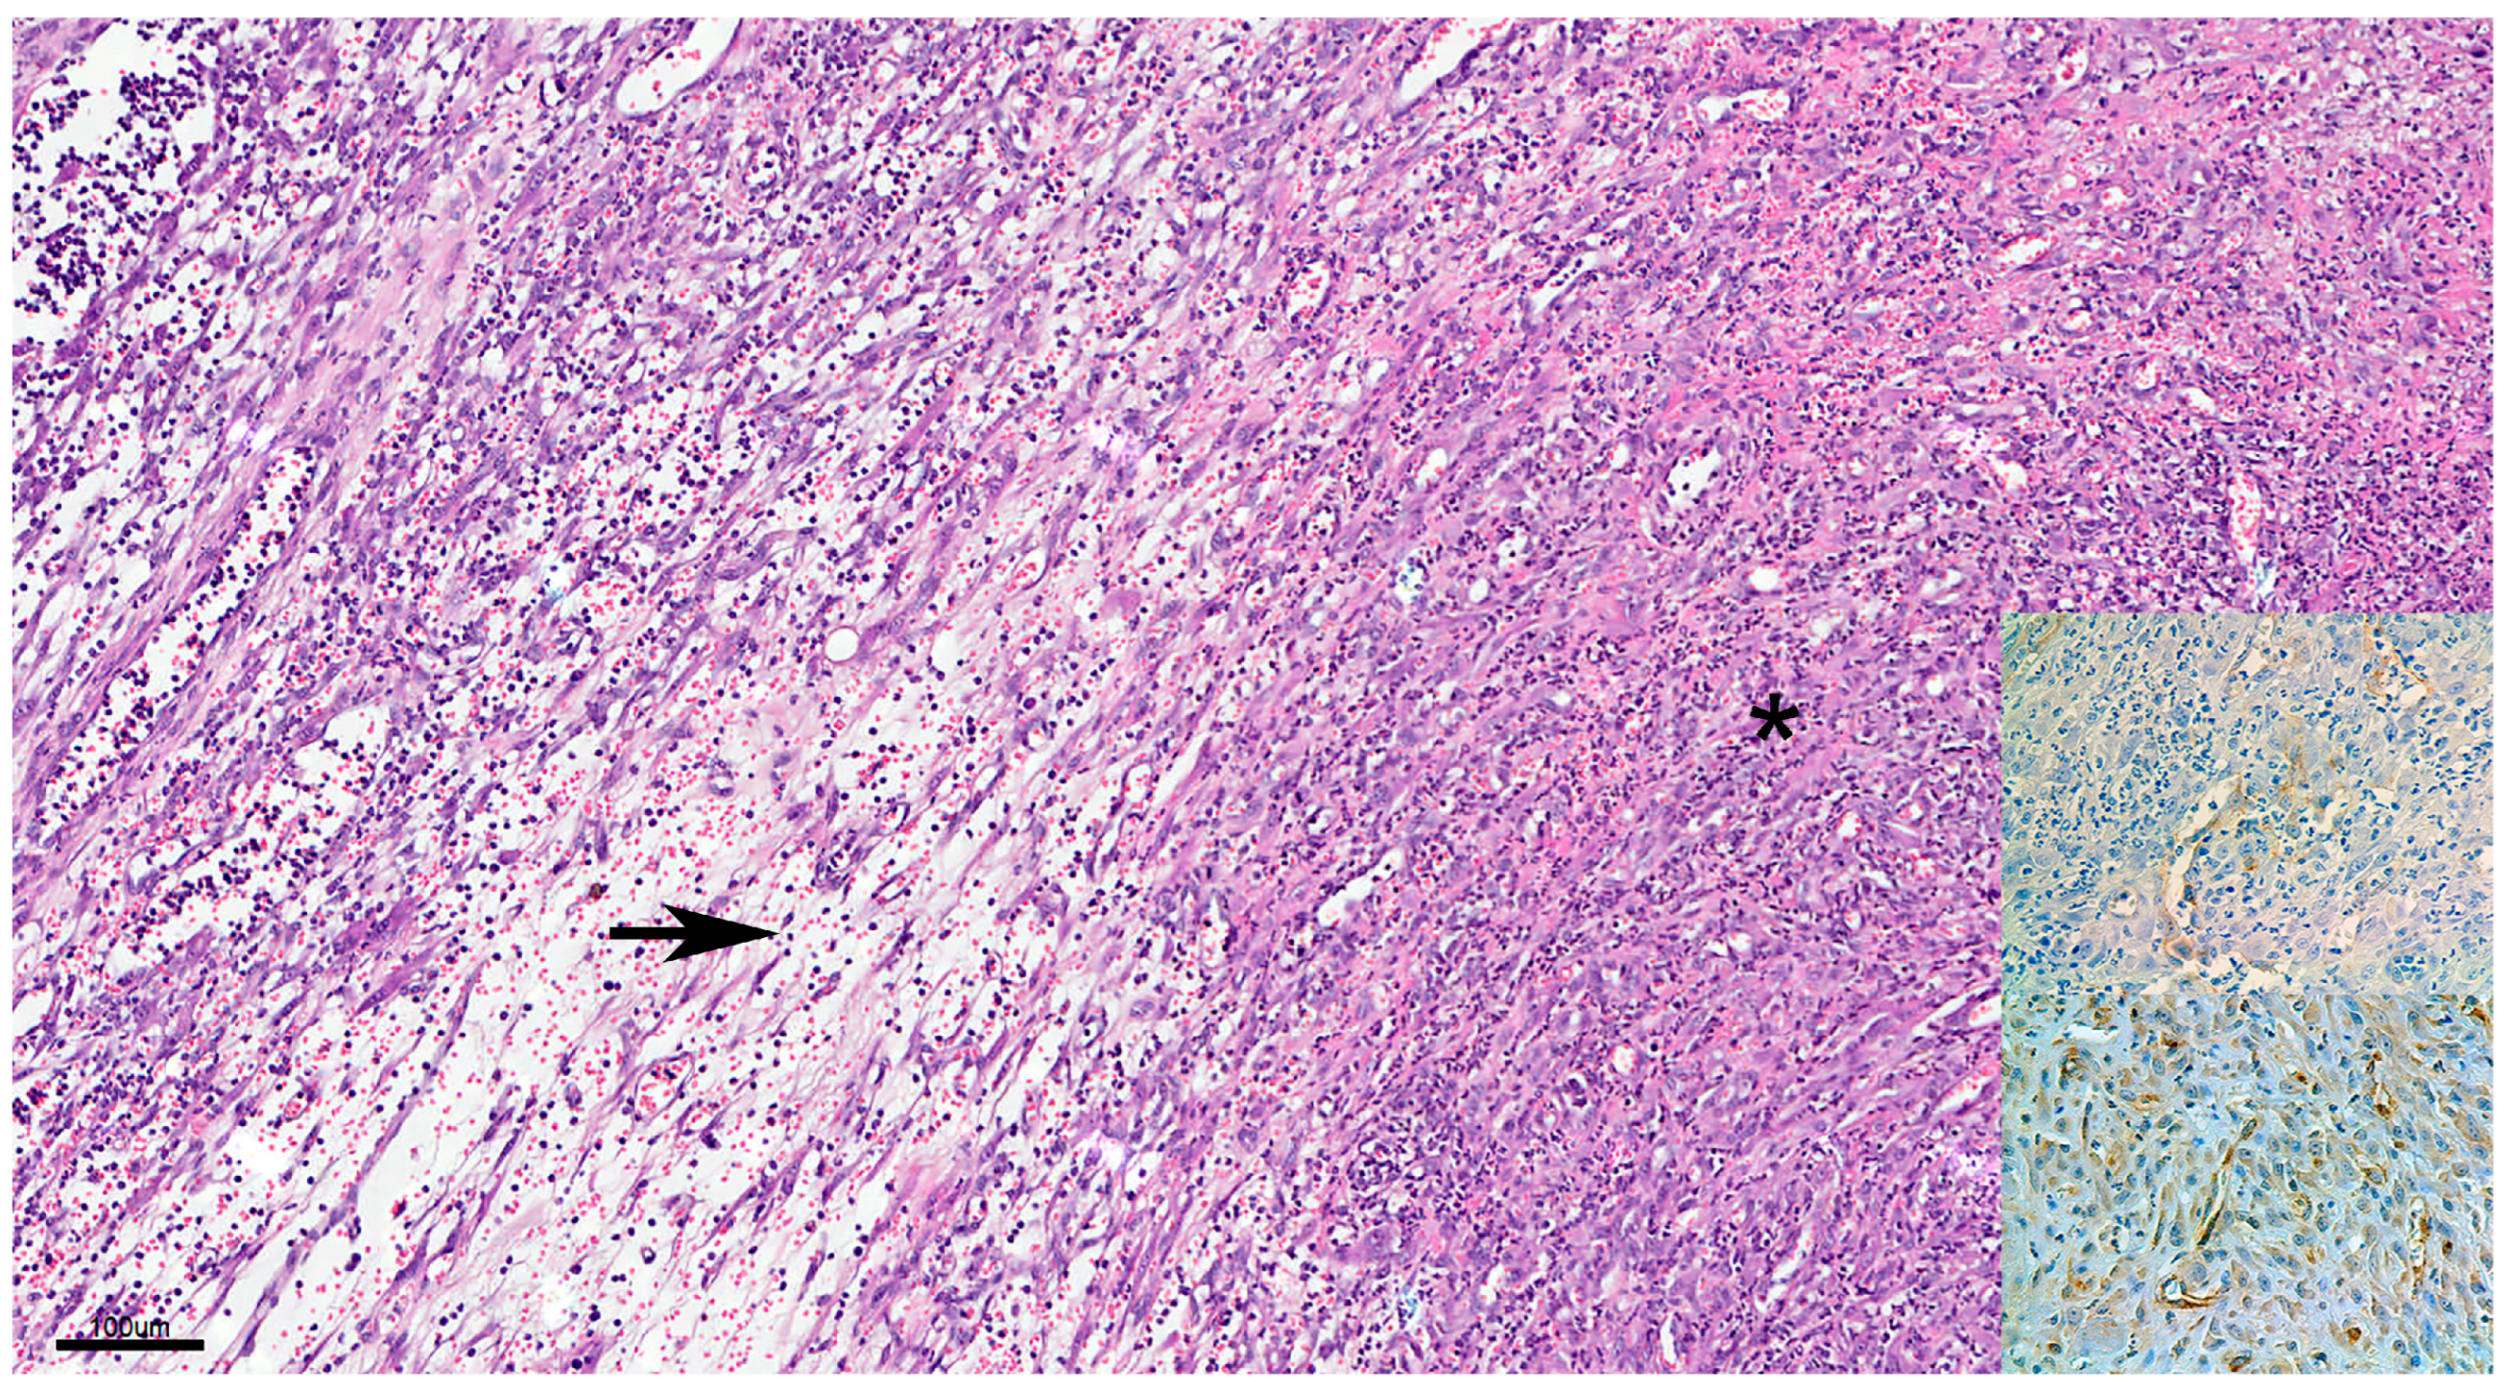

Figure 7.

Cutaneous hemangiosarcoma, mixed type composed of the capillary type at the left side (arrow) and solid and epithelioid types at the right side of the same figure (asterisk). H&E × 40. Upper inset: Strong cytoplasmatic positivity for factor VIII-related antigen × 400. Lower inset: Strong membranous positivity for CD31 × 400. Scale = 100 µm.

Neoplastic cells often have prominent bulging nuclei that are pleomorphic and hyperchromatic with numerous mitoses. Capillary-type tumors are composed of capillary neoplastic endothelial cells that form vascular channels with variable numbers of erythrocytes. Connective tissue surrounding neoplastic vessels is not common. The cavernous type shows an atypical cavernous structure with well-differentiated spindle-shaped cells on a delicate connective tissue framework forming blood-filled cavities and channels. In addition, many cases showed irregularly shaped and sized vessels with neoplastic endothelial cell lining and trabeculae between the vascular lumens. The amount of connective tissue in the stroma varies, and lymphocytes, plasma cells, histiocytic cells, and hemosiderophages are frequently present in the stroma. In the solid type, neoplastic proliferation is composed of solid cords of immature neoplastic cells that have lost the ability to form vascular channels. Although visible vascular structures were rarely observed, some formed neoplastic blood vessels resembling an alveolar-type structure, in which the histologic features included the plump, epithelioid appearance of neoplastic endothelial cells and occasional cytoplasmic vacuolation, which rarely contained erythrocytes. The patterns of epithelioid endothelial cell growth ranged from vasoformative structures to gland/acini-like anaplastic carcinomas, and from short ducts to solid sheets. Regarding histological types, it was rare for each type described above to constitute a tumor alone. Capillary and epithelioid types were observed, whereas the other cases were mixed histological types. Nine capillary, cavernous, and solid mixed types and six cavernous and solid mixed types were observed. In addition, the epithelioid type was observed in seven mixed-type cases. Thrombi were commonly detected in all types, but were more frequent in hemangiomas.

In all types, immunohistochemistry revealed strong membranous staining for CD31 and moderately strong cytoplasmic staining for factor VIII-related antigen in neoplastic cells (Figure 6 and Figure 7). Although the controls used to standardize the immunohistochemistry technique were positive, the tumor cells and internal controls tested negative for the CD34 primary antibody used (Figure 6).